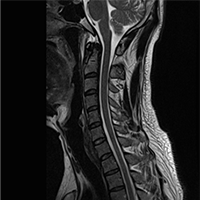

• 정상 경추 MRI

• 경추 5/6 추간판탈출증

(디스크)